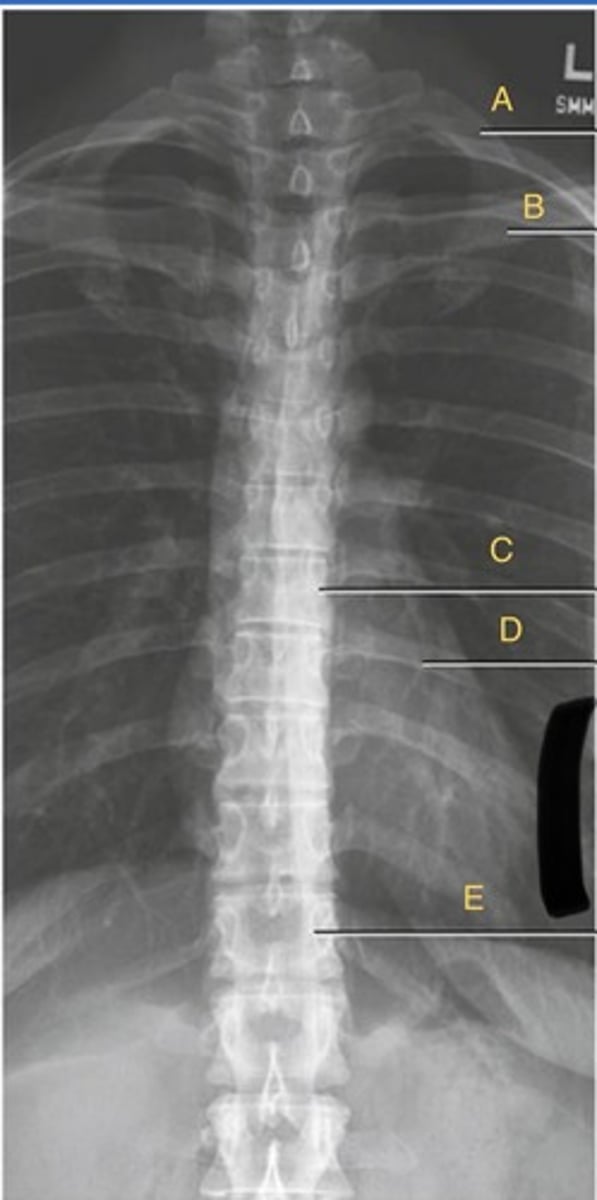

T3-4 intervertebral disk space

B.

T4 transverse process

C.

T5 Pedicle

D.

T7 spinous process

E.

T11 costovertebral joint

F.

T11 inferior articular process

G.

T12 superior articular process

H.

L 1st rib

I.

L 3rd posterior rib

J.

L 9th posterior rib

K

T3 body

A.

T12 floating rib

L